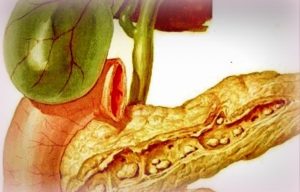

Pancreatitele acute. Pancreatita hemoragică. Simptome, complicații, tratament

Pancreatitele acute sunt afecţiuni ale pancreasului, caracterizate prin leziuni edematoase şi/sau necrotico-hemoragice, cu manifestări clinice dramatice, de unde şi denumirea de dramă pancreatică dată pancreatonecrozelor.

Se diferenţiază mai multe forme de pancreatite acute: edematoasă, hemoragică etc.

Pancreatita hemoragică